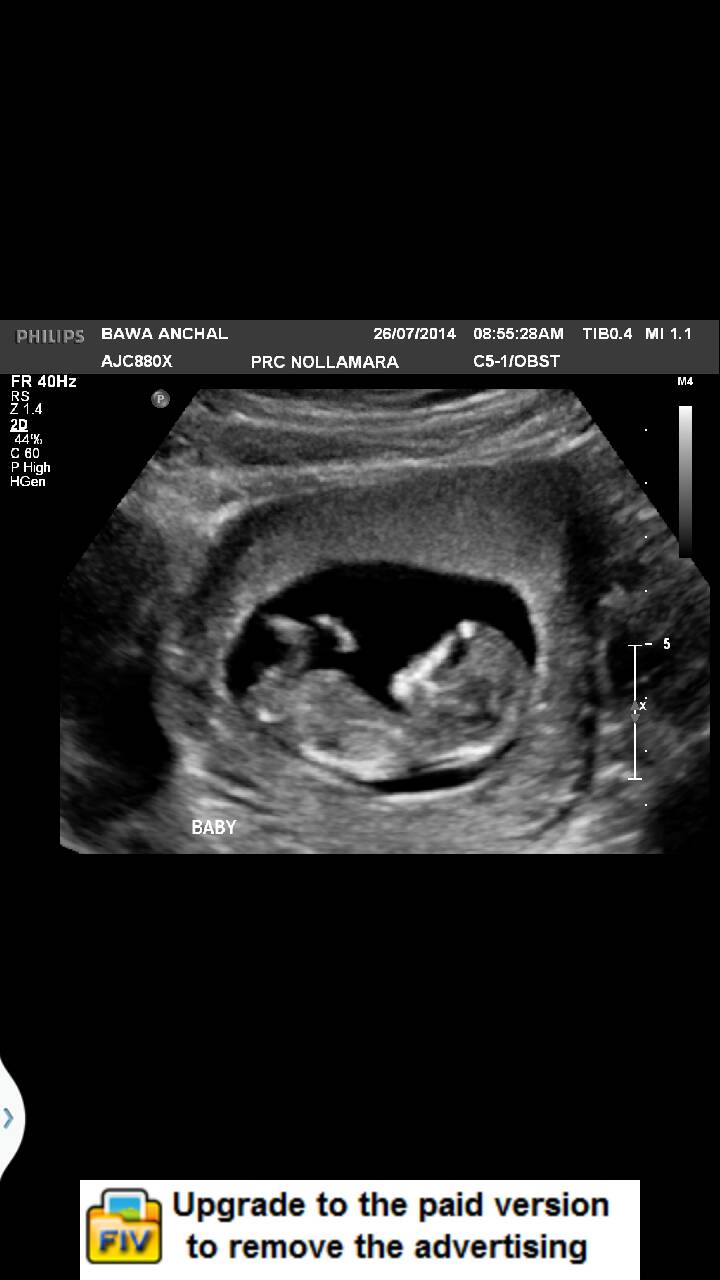

I had my 12 week scan yesterday, I am so exvuted to know what am I carrying. Cab you pkesse ma ke guesses from yh e lovrly images?Attachment 20022Attachment 20022Attachment 20023